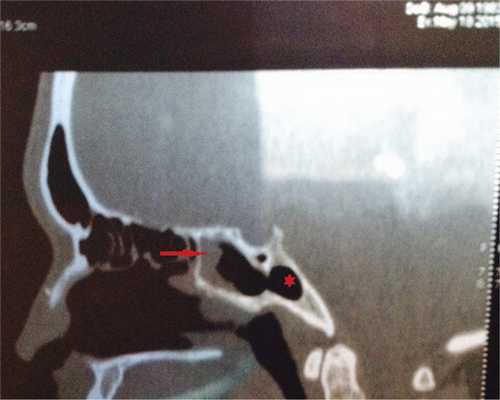

Под общей анестезией в условиях искусственной вентиляции легких с использованием электромагнитной навигационной станции Fusion (фирма «Medtronic», США) были выполнены септопластика и эндоскопическая трансназальная сфенотомия. Навигационная техника использовалась для точного позиционирования места перфорации передней стенки клиновидной пазухи, что в данном случае было актуально из-за особенностей ее анатомии. Расширение естественного соустья выполняли бором с автоматическим орошением и каналом для аспирации, что позволило достаточно быстро и безопасно вскрыть пазуху. При ревизии полости клиновидной пазухи с помощью эндоскопов 45° и 0° определялась неизмененная слизистая оболочка. Использование навигационной станции позволило точно визуализировать расположение предполагаемой кисты (рис. 2). Рис. 2. Пациентка Н. Интраоперационная визуализация (данные с монитора навигационной станции) позволила хирургу с высокой точностью определить локализацию патологического процесса (обозначено звездочкой). Fig. 2. Patient N. The intraoperative visualization (available at the monitor of the navigation station) enabled the surgeon to accurately locate the pathological process (indicated by the asterisk). Она локализовалась в отдельной ячейке (в затылочном кармане), сообщающейся с пазухой отверстием до 7 мм в диаметре. При удалении киста опорожнилась, содержимое — густой гной.

Послеоперационный период протекал гладко. При контрольной компьютерной томографии околоносовых пазух, проведенной через 7 дней после хирургического вмешательства, отмечались реактивные изменения слизистой оболочки клиновидной пазухи в области передней стенки (рис. 3). Рис. 3. Компьютерная томограмма пациентки Н. на 7-е сутки после операции. Fig. 3. Computed tomography of patient N. on day 7 after surgery. Отмечается незначительное реактивное утолщение слизистой оболочки клиновидной пазухи в области расширенного соустья и по передней стенке (указано стрелкой), патологическое образование удалено (обозначено звездочкой). An insignificant reactive thickening of the mucous membrane of the sphenoidal sinus is fairly well apparent near the broadened opening and along the anterior wall (indicated by the asterisk), the pathologically altered structure is removed (indicated by the asterisk). При контрольном осмотре через 1 мес пациентка отметила полное исчезновение жалоб, а также значительное улучшение общего самочувствия.